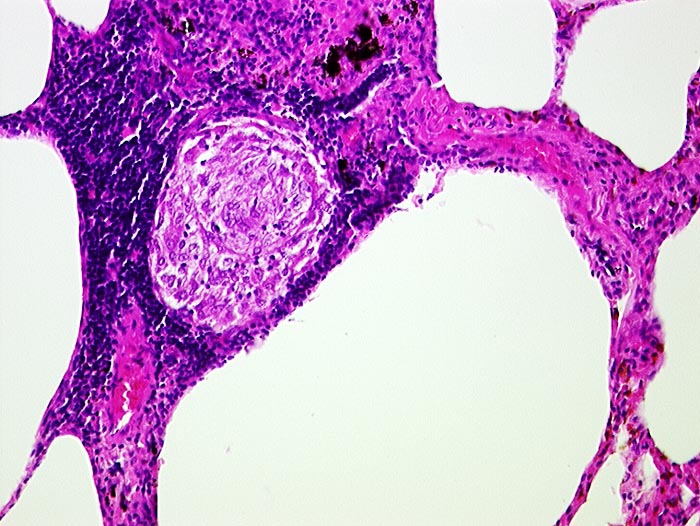

Die Morphologie der Erkrankung ist stadienabhängig. Initial findet sich eine lymphozytenreiche Alveolitis mit wenigen kleinen Granulomen. Die Granulome bestehen aus Aggregaten epitheloider Histiozyten teilweise mit Beteiligung von mehrkernigen Riesenzellen. Im Verlauf entwickeln sich zellreiche Granulome entlang der bronchovaskulären Bündel und der Interalveolarsepten, welche später konfluieren und vernarben. Die Riesenzellen können Asteroidkörperchen (sternförmige Kristalle) oder Schaumannkörperchen (lamelläre Verkalkungen) enthalten. Ein Teil der Patienten entwickelt eine irreversible Lungenfibrose.

• Zahlreiche produktive, nicht nekrotisierende Granulome aus dickleibigen Epitheloidzellen, Riesenzellen vom Langhanstyp und Lymphozyten.

• Ausgeprägte Fibrosierung der Granulome.

• Bevorzugte Lokalisation der Granulome im Bereich von Bronchiolen und Pulmonalarterienästen. Das sollte der Kliniker dem Pathologen mitteilen: